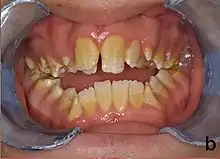

Amelogenesis imperfecta, hypoplastic type. Note the association of pitted enamel and open bite. | |

People with amelogenesis imperfecta may have teeth with abnormal color: yellow, brown or grey; this disorder can affect any number of teeth of both dentitions. Enamel hypoplasia manifests in a variety of ways depending on the type of AI an individual has (see below), with pitting and plane-form defects common.[4] The teeth have a higher risk for dental cavities and are hypersensitive to temperature changes as well as rapid attrition, excessive calculus deposition, and gingival hyperplasia.[5] The earliest known case of AI is in an extinct hominid species called Paranthropus robustus, with over a third of individuals displaying this condition.[6]